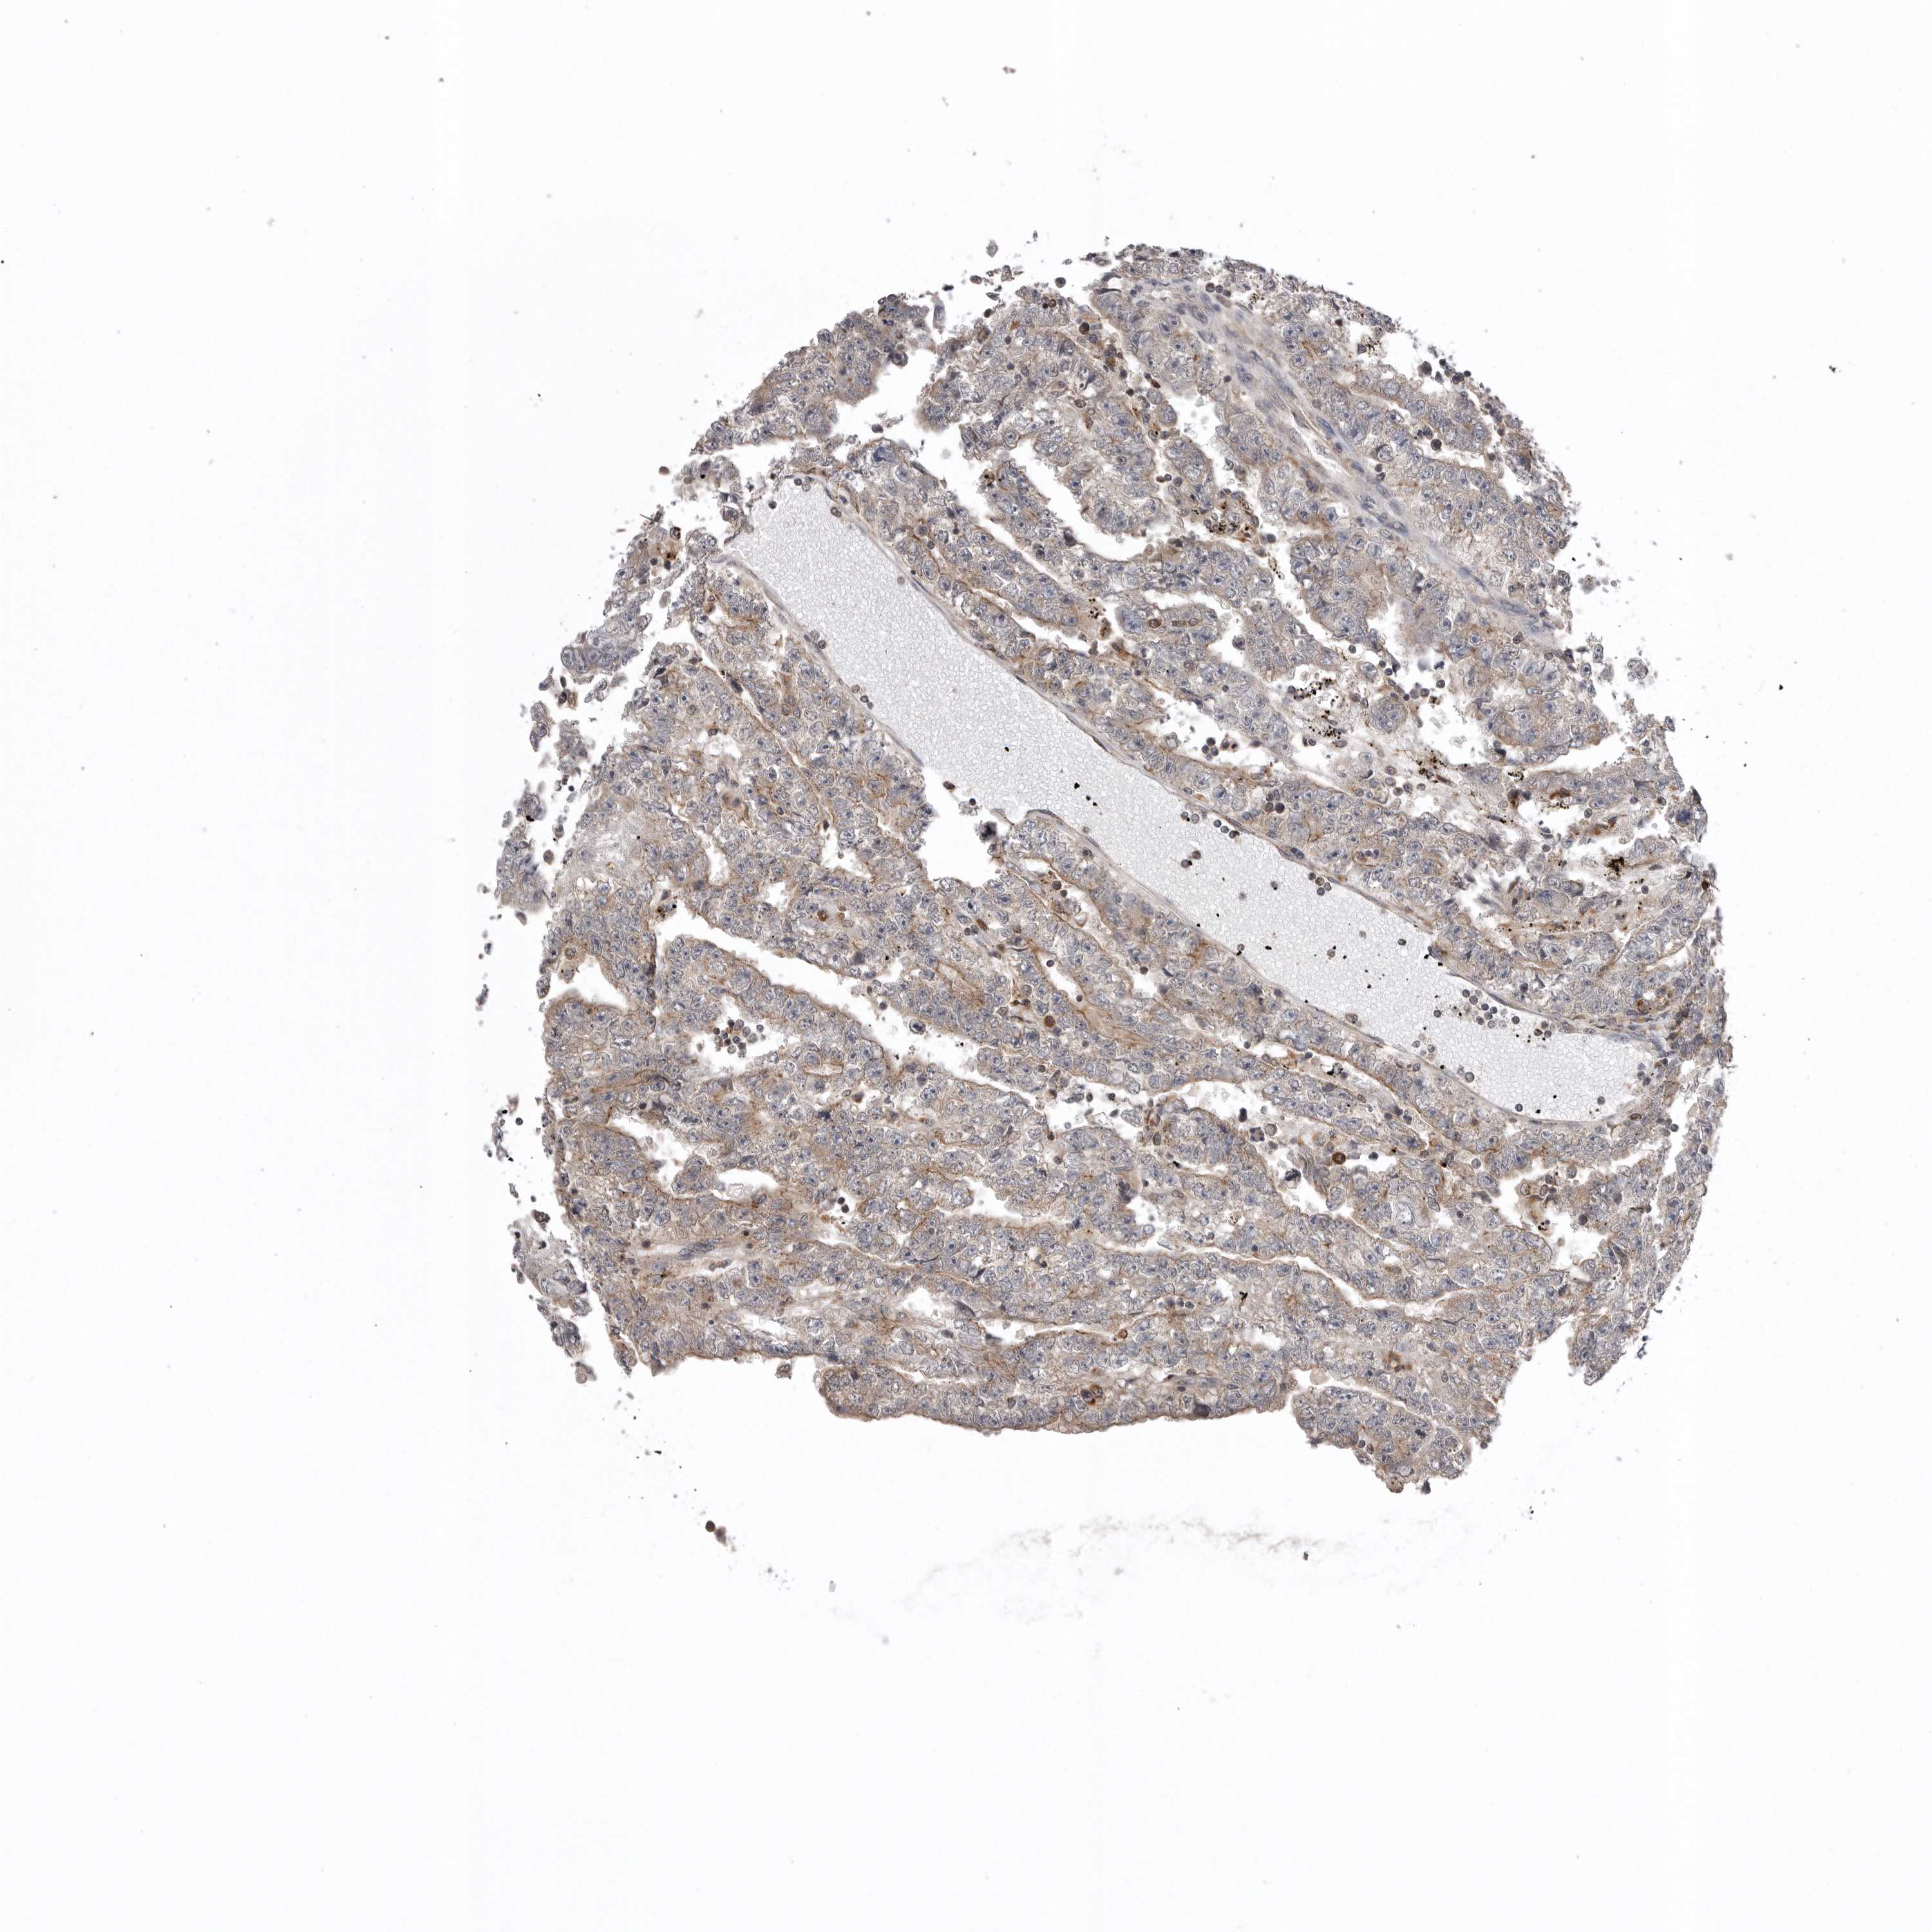

TESTIS CANCER - Protein expressioni

A mouse-over function shows sample information and annotation data. Click on an image to view it in a full screen mode. Samples can be filtered based on level of antibody staining by selecting one or several of the following categories: high, medium, low and not detected. The assay and annotation is described here.

Note that samples used for immunohistochemistry by the Human Protein Atlas do not correspond to samples in the TCGA dataset.

Antibody stainingi

Antibody staining in the annotated cell types in the current human tissue is reported as not detected, low, medium, or high, based on conventional immunohistochemistry profiling in selected tissues. This score is based on the combination of the staining intensity and fraction of stained cells.

Each image is clickable and will lead to virtual microscopy that enables deeper exploration of all samples and also displays staining intensity scores, fraction scores and subcellular localization as well as patient and tissue information for each sample.

Antibody HPA021666

Antibody HPA026716

Staining

High

Medium

Low

Not detected

Intensity

Strong

Moderate

Weak

Negative

Quantity

>75%

75%-25%

<25%

None

Location

Nuclear

Cytoplasmic/membranous

Cytoplasmic/membranous,nuclear

Carcinoma, Embryonal, NOS

Seminoma, NOS